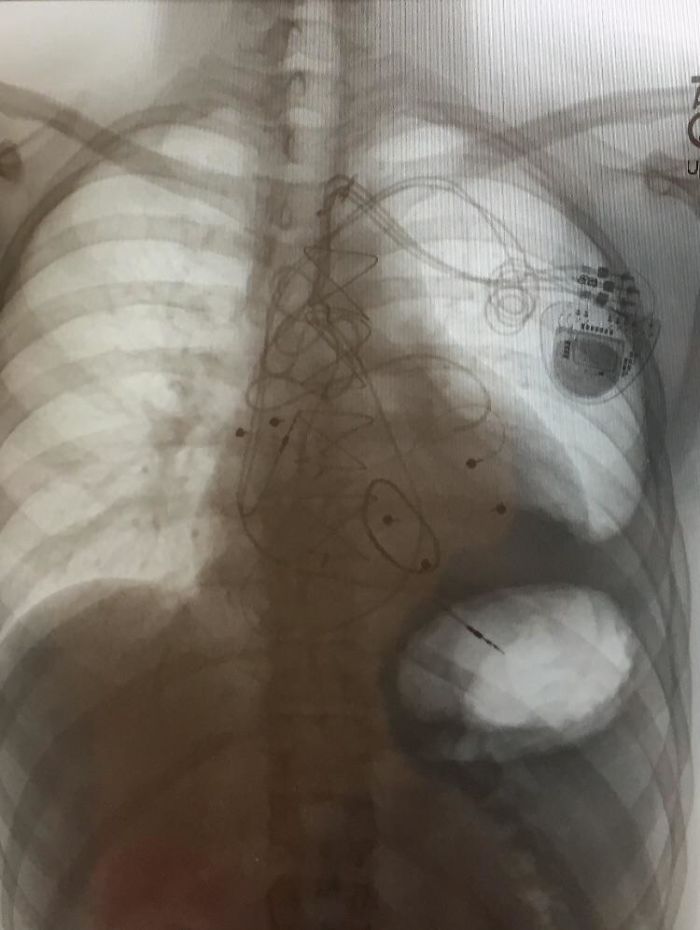

My Chest X-Ray After 3 Pacemaker Surgeries, A Median Sternotomy And Valve Repair